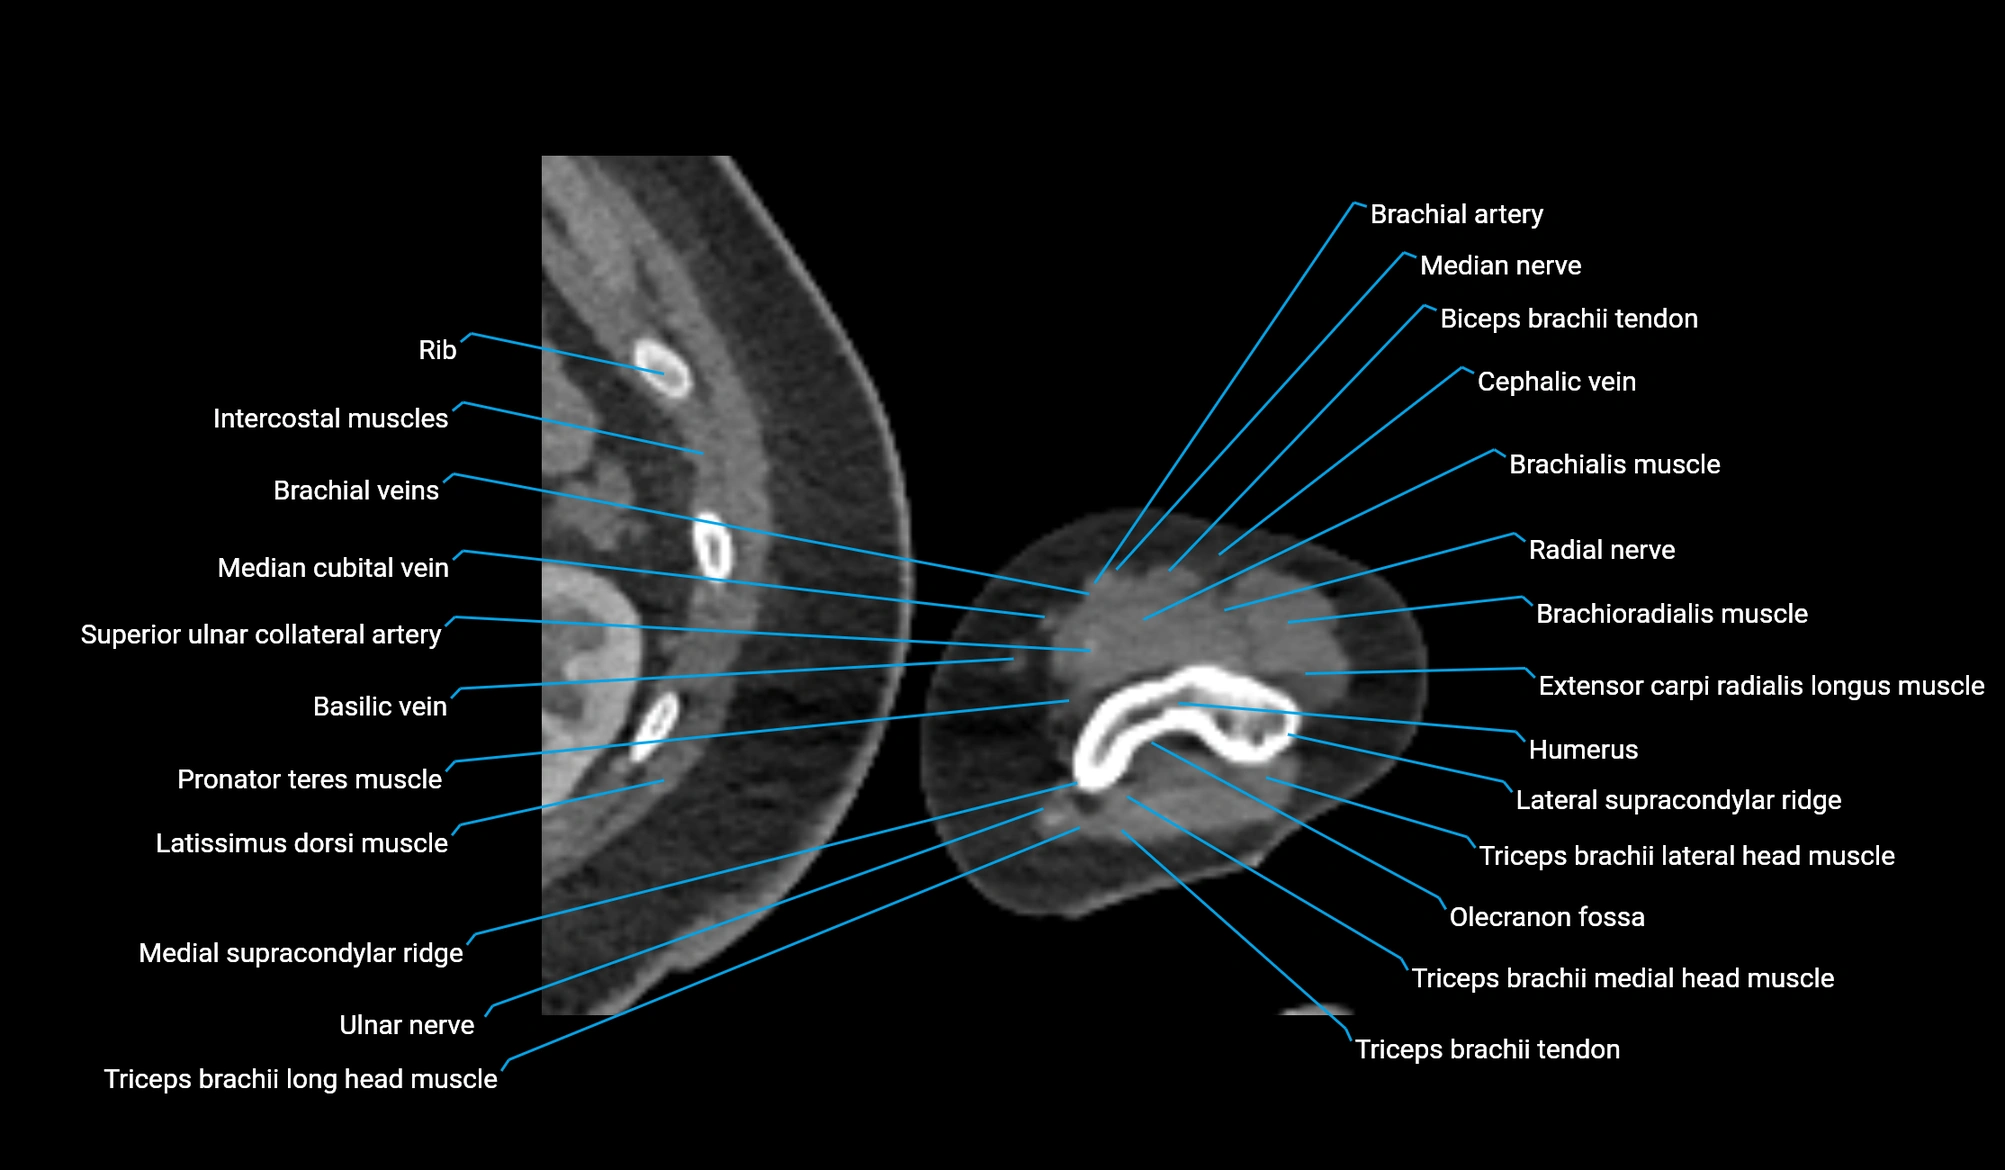

CT image